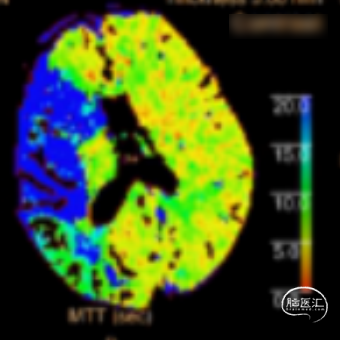

术前CTA+CTP示:1.右侧大脑中动脉M1段闭塞,前交通开放,右侧后交通开放;2.右侧大脑中动脉供血区大面积TTP、MTT延长,CBF降低,CBV减低。